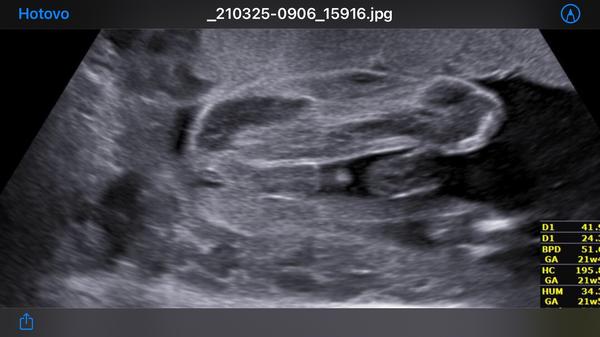

Kluk nebo holka? 🥰

Kluk. U holky by bylo kávové zrno víc "uprostřed spodku", tohle hodně vyčnívá dopředu (ty kulky).

Taky si myslím, že z tohohle už holčičku neuděláš :D Jako ten náš... Tenhle pohled, co máš na fotce, mám já pokaždé na ultrazvuku. Náš malej je snad exhibicionista 😅